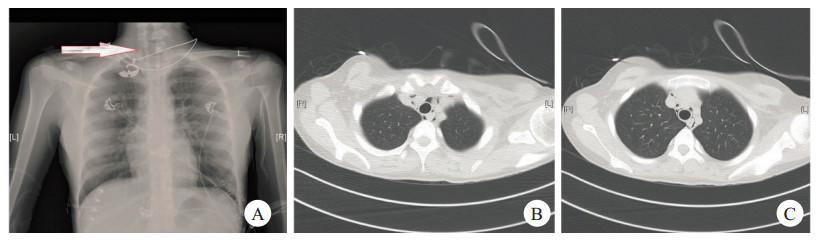

1 资料与方法 1.1 一般资料患者女性,18岁,主因“腹部不适10 d,呕吐5 d”来诊。既往体健,否认糖尿病史。入院查体:体温36.0℃,脉搏72次/min,呼吸18次/min,血压101/60 mmHg。双肺呼吸音清,未闻及干湿啰音,无胸膜摩擦音。心律齐,各瓣膜区未闻及杂音,无心包摩擦音。腹软,无压痛、反跳痛、肌紧张。双下肢无水肿。辅助检查:血糖29.8 mmol/L,尿糖4+,尿酮体4+。血气分析示:酸碱度7.15,二氧化碳分压15.0(mmHg),氧分压116.0(mmHg);血常规:白细胞14.51×109/L, 红细胞5.98×1012/L,血红蛋白183.0 g/L,红细胞压积0.5,血小板374.0×109/L;血肝功、肾功、电解质均正常;患者入院后仍有间断呕吐,诉有胸痛,立即予以胸片检查,胸片(图 1A):双肺纹理增多,纵隔气肿待排;查胸部CT(图B, C):颈部、纵隔积气。

| 图 一 颈部可见低密度影(箭头处) |